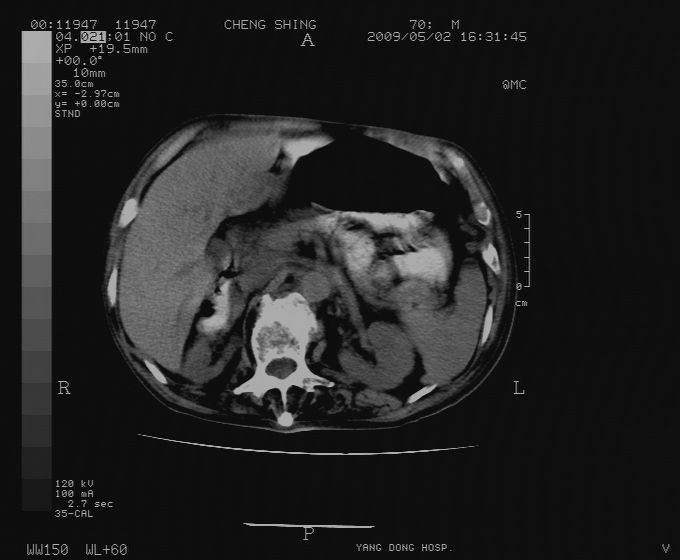

标题: CT19743:男70岁,肺部疾病入院,B超发现肝右叶占位,CT [打印本页]

标题: CT19743:男70岁,肺部疾病入院,B超发现肝右叶占位,CT

肝表面塌陷,病灶周围有子灶,前面较大子灶强化符合肝癌表现,考虑肝癌肝转移可能性大.

1.考虑肝癌肝转移

2.两侧胸水,左下肺不张!

1)考虑肝癌并肝内转移。2)少量腹水。3)双侧胸腔积液。

1)考虑肝癌并肝内转移。2)少量腹水及双侧胸腔积液。3)椎体退变。